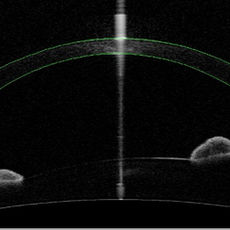

La topografia corneale è l'esame d'elezione per la diagnosi e lo studio dell'evoluzione del cheratocono. Si tratta di uno strumento che analizza i dati derivati dalla riflessione di anelli luminosi concentrici (disco di Placido) proiettati sulla cornea e li trasforma in mappe colorate (topografiche) che ne descrivono la forma e la regolarità della superficie anteriore. Attraverso questo esame è possibile evidenziare tutte le alterazioni di riflessione della cornea e riconoscere anomalie, anche molto iniziali della curvatura corneale.

Il secondo esame fondamentale è rappresentato dalla pachimetria corneale (misurazione dello spessore centrale) che si ottiene con una sonda a ultrasuoni o con metodiche ottiche.

Una metodica recente è rappresentata dalla tomografia corneale con lampada rotante di Scheimpflug che consente un’analisi della cornea in tre dimensioni inclusa la superficie posteriore; questa metodica consente una diagnosi più precoce in caso di forme iniziali di cheratocono oltre che una pachimetria ottica in ogni singolo punto.